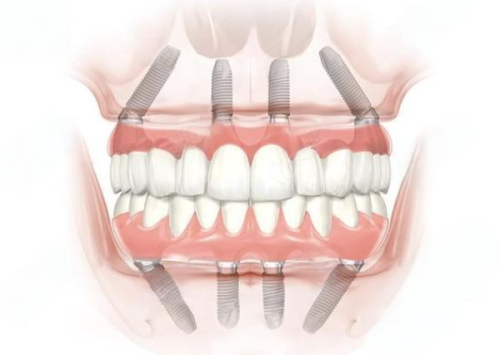

种植牙一般指的是种植义齿,它是目前比较理想的牙齿修复方式。特别多人都想知道种植牙多少钱一颗,总体来说,种植牙的价格通常在5000元 - 20000元一颗。不过这个价格范围跨度较大,因为种植牙的费用受到多种因素的影响。

患者的颌骨条件也是影响种植牙多少钱一颗的重要因素。如果患者颌骨条件良好,骨量充足,那么在进行种植牙手术时就相对简单,不需要额外的处理,这种情况下,种植牙的价格可能在5000元 - 10000元一颗。然而,有些患者由于长期缺牙、牙槽骨吸收等原因,颌骨条件不足,在进行种植牙手术前,需要精良行骨移植或上颌窦提升术等额外的手术,以增加骨量,为种植牙提供良好的基础。这样一来,手术的难度和复杂度增加,费用也会相应提高,一般需要10000元 - 20000元一颗。